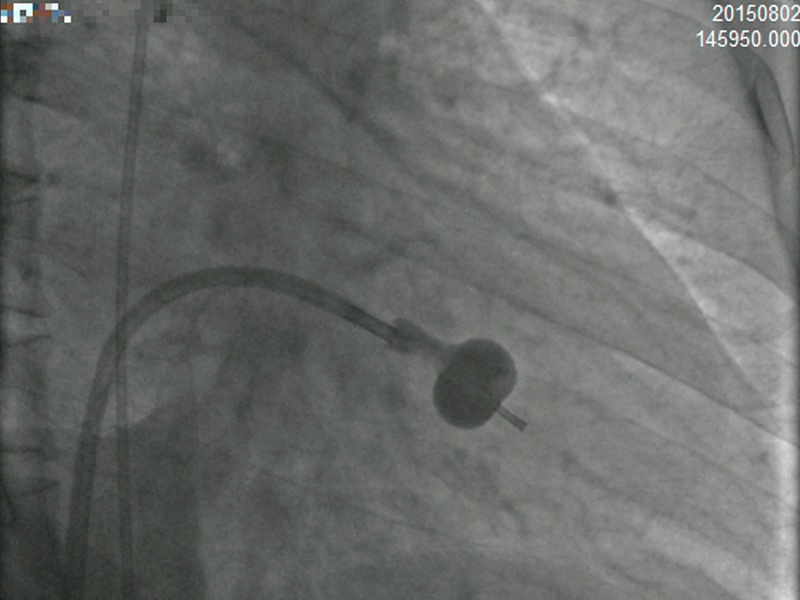

It is a minimally invasive procedure. A thin tube called catheter is inserted through an artery in the groin/arm and it is threaded to the heart. The catheter is directed to the mitral valve. A balloon device located at the tip of this tube is inflated quickly. The narrowed mitral leaflets are stretched open, thus increasing the size of the mitral valve opening. So more blood flows from the left atrium to the left ventricle.